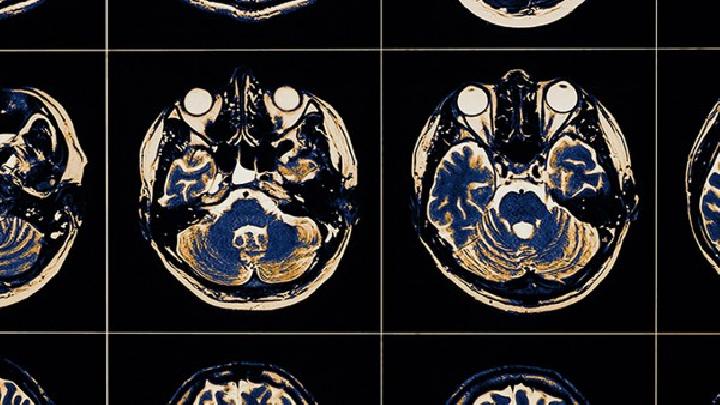

脑电图和脑诱发电位与原发颅脑创伤有关的异常结果可以检测到。CT、根据患者脑外伤的不同情况,如气脑造影有相应的变化。